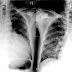

Tamponade can often be diagnosed radiographically. Echocardiography, which is the diagnostic test of choice, often demonstrates an enlarged pericardium or collapsed ventricles. A large cardiac tamponade will show as an enlarged globular-shaped heart on chest x-ray. During inspiration, the negative pressure in the thoracic cavity will cause increased pressure into the right ventricle. This increased pressure in the right ventricle will cause the interventricular septum to bulge towards the left ventricle, leading to decreased filling of the left ventricle. At the same time, right ventricle volume is markedly diminished and sometimes it can collapse.